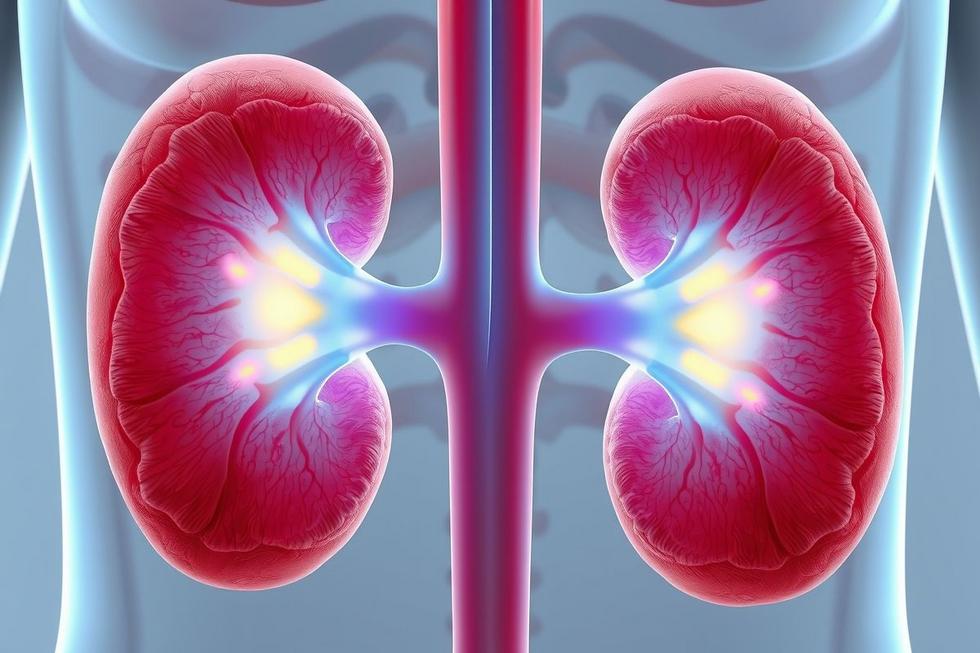

A pielonefrite é uma infecção que afeta um ou ambos os rins, sendo classificada como aguda ou crônica. A forma aguda ocorre rapidamente, enquanto a crônica se desenvolve ao longo do tempo, frequentemente após múltiplos episódios de infecções. Essa condição pode levar à inflamação dos tecidos renais e, em casos mais graves, à deterioração da função renal.

Para entender melhor a pielonefrite, é essencial conhecer a anatomia dos rins. Os rins são órgãos em forma de feijão localizados na parte posterior da cavidade abdominal. Eles são responsáveis pela filtração do sangue, remoção de resíduos e regulação do equilíbrio eletrolítico e hídrico do corpo. Quando uma infecção se instala, o tumor renal responde com uma reação inflamatória, causando dor, inchaço e comprometendo sua função. Essa infecção pode resultar em danos irreversíveis se não tratada adequadamente.